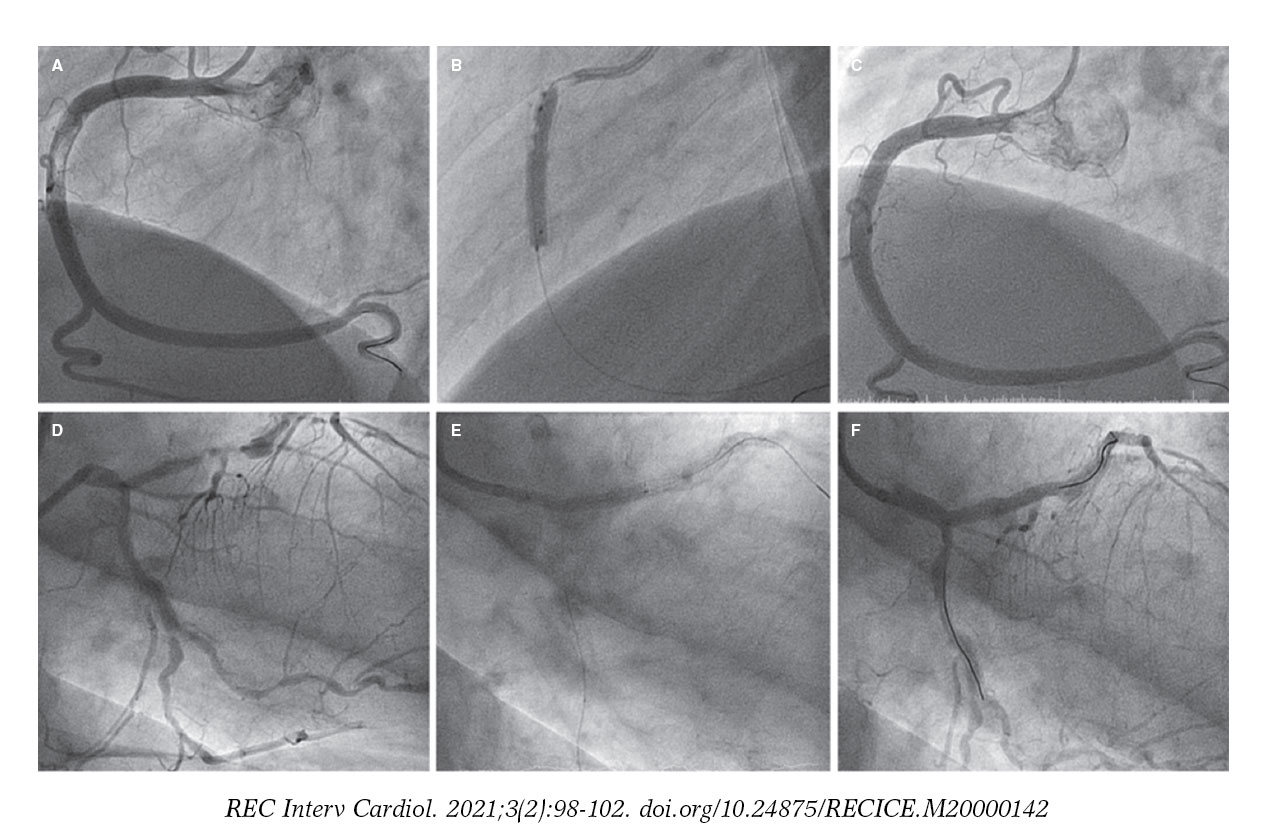

Coronary Angiogram Images A The Intra Stent Thrombosis Of The Download Scientific Diagram

Thrombosis And Acute Myocardial Infarction As Consequences Of Very Late Stent Malapposition After Implantation Of A Drug Eluting Journal Of Invasive Cardiology